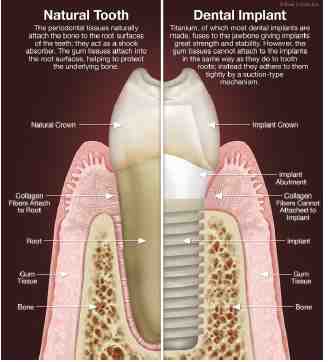

Mini implants are one of the most advanced and effective solutions for replacing natural teeth. This may interest you : Dental Implants Milwaukee. They can be a solution for those who have significant bone loss or are looking for a more affordable option for full dental implants.